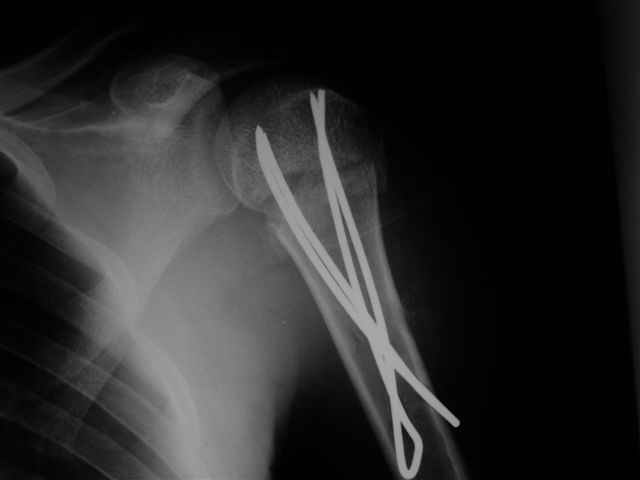

Женя, а как ты водишь спицы, в смысле, как делаешь входное отверстие, и как в него проводишь V-спицу? А то о дна из спиц, та, у которой не дошла до головки одна палочка буквы V, как-то выглядит на рентгенограмме, как будто или через очень большое отверстие введена, или каждая половинка через отдельные отверстия.

Мне кажется, проблема в том, что не все концы спиц зашли в головку, и зашедшие - недостаточно далеко прошли.

Спицы провожу по передней и задней поверхностям плечевой кости через 4,5 мм отверстия на разных уровнях.

Идеей презентации случая была демонстрация важности постоп Рг - хотя казалось бы все было сделано под флюороскопическим контролем и интраоперационно подозрений на нестабильность не возникло, а такая вот

неожиданность...

Уточни - обе части буквы V вводишь в одно отверстие? А то по снимкам выглядит, что в разные.

V-спица проводится через 4,5 мм отверстие. Видимо, из-за разной длины вторая половина спицы *пролетела* мимо отверстия, что и привело к вторичному смещению костных фрагментов.